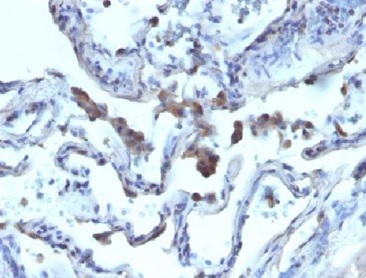

Immunohistochemistry (Formalin/PFA-fixed paraffin-embedded sections) - Anti-AMACR antibody [AMACR/1723] (AB219309)

Immunohistochemical analysis of formalin-fixed paraffin-embedded human prostate carcinoma tissue labeling AMACR with ab219309 at 2 μg/ml.